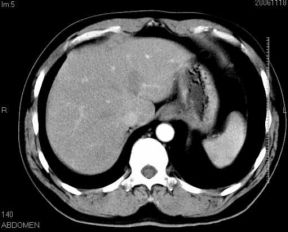

男性,48岁

肝内占位,性质?

肝内多发低密度占位病变,边缘清晰,无强化,肝转移瘤可能

肝内多发低密度占位病变,边缘清晰,无强化,肝转移瘤可能大,请将胃喝水充盈以后再扫描看看,我看大弯侧胃壁较厚。

肝内多发不规则形状低密度灶,强化不明显,考虑转移,积极查找原发灶

肝内多发低密度类圆形病灶,边缘清晰.增强无强化.

意见:1,考虑多发转移瘤;

2,囊肿与血管瘤不排除.

1肝内多发低密度影,考虑:转移瘤 2胃大弯侧胃壁明显增厚,建议胃镜检查除外胃癌